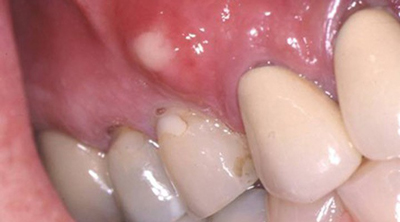

کیست دهان به برآمدگی های ایجاد شده اطراف و درون دهان گفته می شوند. در حقیقت کیست، کیسه ای بافتی حاوی مایع یا موادی دیگر است که ممکن است روی لب، گونه، لثه و فک ایجاد شود. به کیست نزدیک دندان کیست دندان نیز گفته می شود.

کیست بافت نرم توده‌ای کوچک و بدون درد بوده که قطر آن عمدتا کمتر از یک اینچ است. کیست زیر پوست داخل لب پایین، درون گونه‌ها یا لثه‌ها ایجاد می‌شود. کیست معمولاً بدون درد است، مگر آن که عفونی باشد. کیست کوچک ادنتوژنیک داخل فک بدون درد است. اگر کیست ادنتوژنیک بزرگ و عفونی شود، دردناک نیز خواهد شد. کیست باعث برجسته شدن استخوان فک، لق شدن و حرکت دندان نیز خواهد شد.

این نوع کیست غالبا روی لثه ایجاد می‌شود و بر ساختار استخوانی دندان تاثیر مستقیم نمی گذارد.